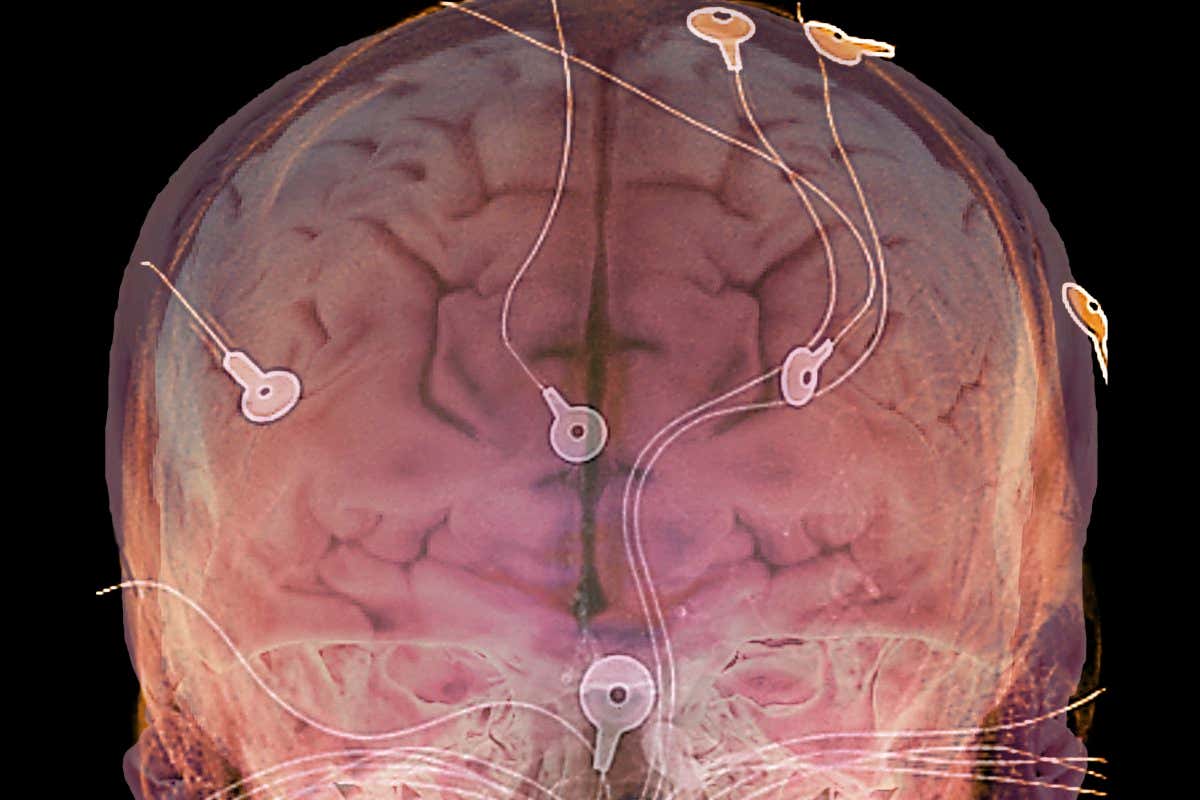

A brain implant used to treat epilepsy could be used on other conditions ZEPHYR/SCIENCE PHOTO LIBRARY

Electrical brain stimulation in people with pre-existing brain implants has allowed them to think more flexibly and clear anxious thoughts, suggesting it has the potential to treat conditions like depression.